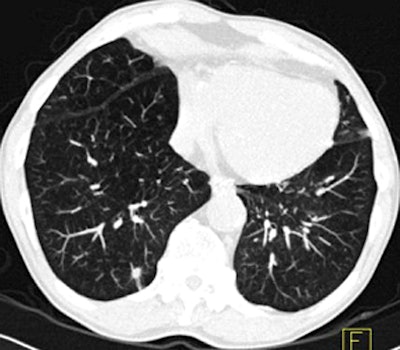

| Images above and below show a spiculated nodule measuring 169 mm3 at baseline low-dose CT screening. Bottom image, acquired four years after the baseline scan, shows that the nodule has resolved. All images courtesy of Dr. Rosemarijn Vliegenthart. |